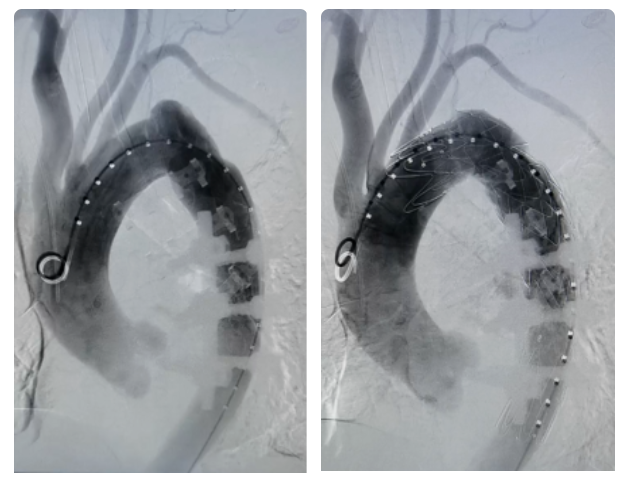

考虑到患者年龄,最终团队决定为患者实施主动脉腔内修复术——即从血管内释放覆膜支架“堵住”动脉瘤,只需要在患者腹股沟部位做一个很小的切口进行穿刺操作,术后恢复较快,达到“微创”修复的目的。

但是更大的难题摆在了医护团队面前,患者的主动脉弓属于最为陡峭的Ⅲ型弓,操作中易发生支架定位失败甚至瘤体破裂;患者既往外伤遗留钢板和钢钉阻挡术中透视视野,影响定位;且患者动脉瘤内附着血栓随时有脱落的风险,大大增加了手术难度。

在完善术前检查后,陆大妈被送往介入手术室。在李鑫教授主刀下行经股动脉胸主动脉覆膜支架腔内隔绝术+腹主动脉造影术,仅仅1个小时完成手术。陆大妈醒来后发现右腹股沟的伤口并没有想象中疼痛,并且当天就恢复了饮食,术后第二天便下床活动,复查CT显示瘤体隔绝良好,陆大妈连连惊叹:“手术效果真不错,国际知名专家团队果然名不虚传!”目前,陆大妈已经顺利康复出院。